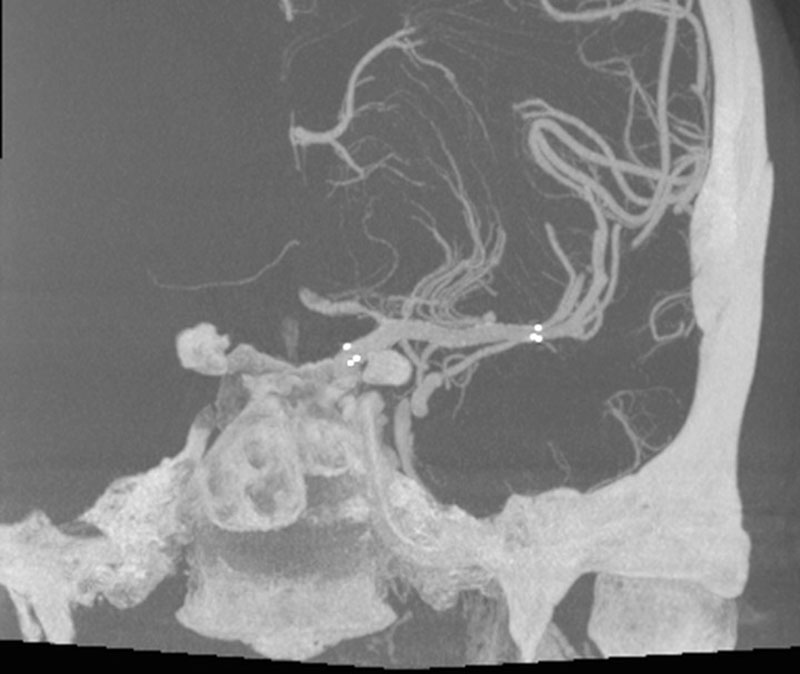

VASO-CT post

DSA

L - ICA